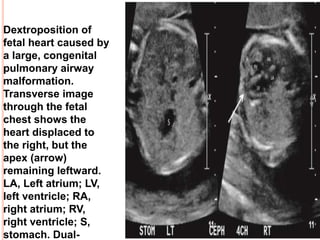

Dextroposition of

fetal heart caused by

a large, congenital

pulmonary airway

malformation.

Transverse image

through the fetal

chest shows the

heart displaced to

the right, but the

apex (arrow)

remaining leftward.

LA, Left atrium; LV,

left ventricle; RA,

right atrium; RV,

right ventricle; S,

stomach. Dual-